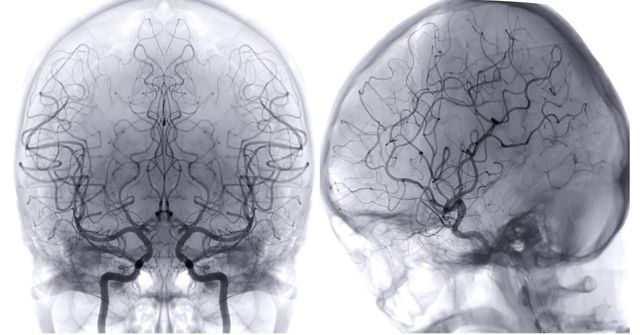

기사의 이해를 돕기 위한 이미지. / Radiological imaging-shutterstock.com